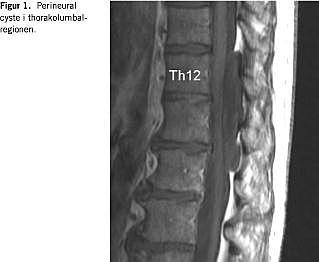

I. En 51-årig mand fik over et år tiltagende kraftnedsættelse og styringsbesvær i begge ben. Der var tiltagende atrofi af muskulaturen på begge lår, mest udtalt på højre side. Patienten blev primært undersøgt på mistanke om motorneurone sygdomme, hvilket ikke kunne påvises. Ved en magnetisk resonans (MR)-skanning af columna torakolumbalis sås en intraspinal ekstradural cystisk proces ud for 12. brysthvirvel til anden lændehvirvel beliggende dorsalt for durasækken (Figur 1 ). Ved operation fandtes en stor cystisk proces, der komprimerede durasækken. Cysten var blød og kompressibel. Den midterste del af cysten var stilket til durasækken. Cysten blev åbnet, og der fandtes en lille defekt på venstre side, hvor der undslap ganske lidt væske. Det meste af cysten blev excideret. De tilbageblevne flapper blev lukket hen over defekten og lukket med fibrinklæber. Feltet var herefter tørt. Ved kontrol fire måneder senere var patienten fuldt restitueret og havde genoptaget sit arbejde som murer. Ved en kontrol-MR-skanning blev det konstateret, at cysten ikke havde gendannet sig.